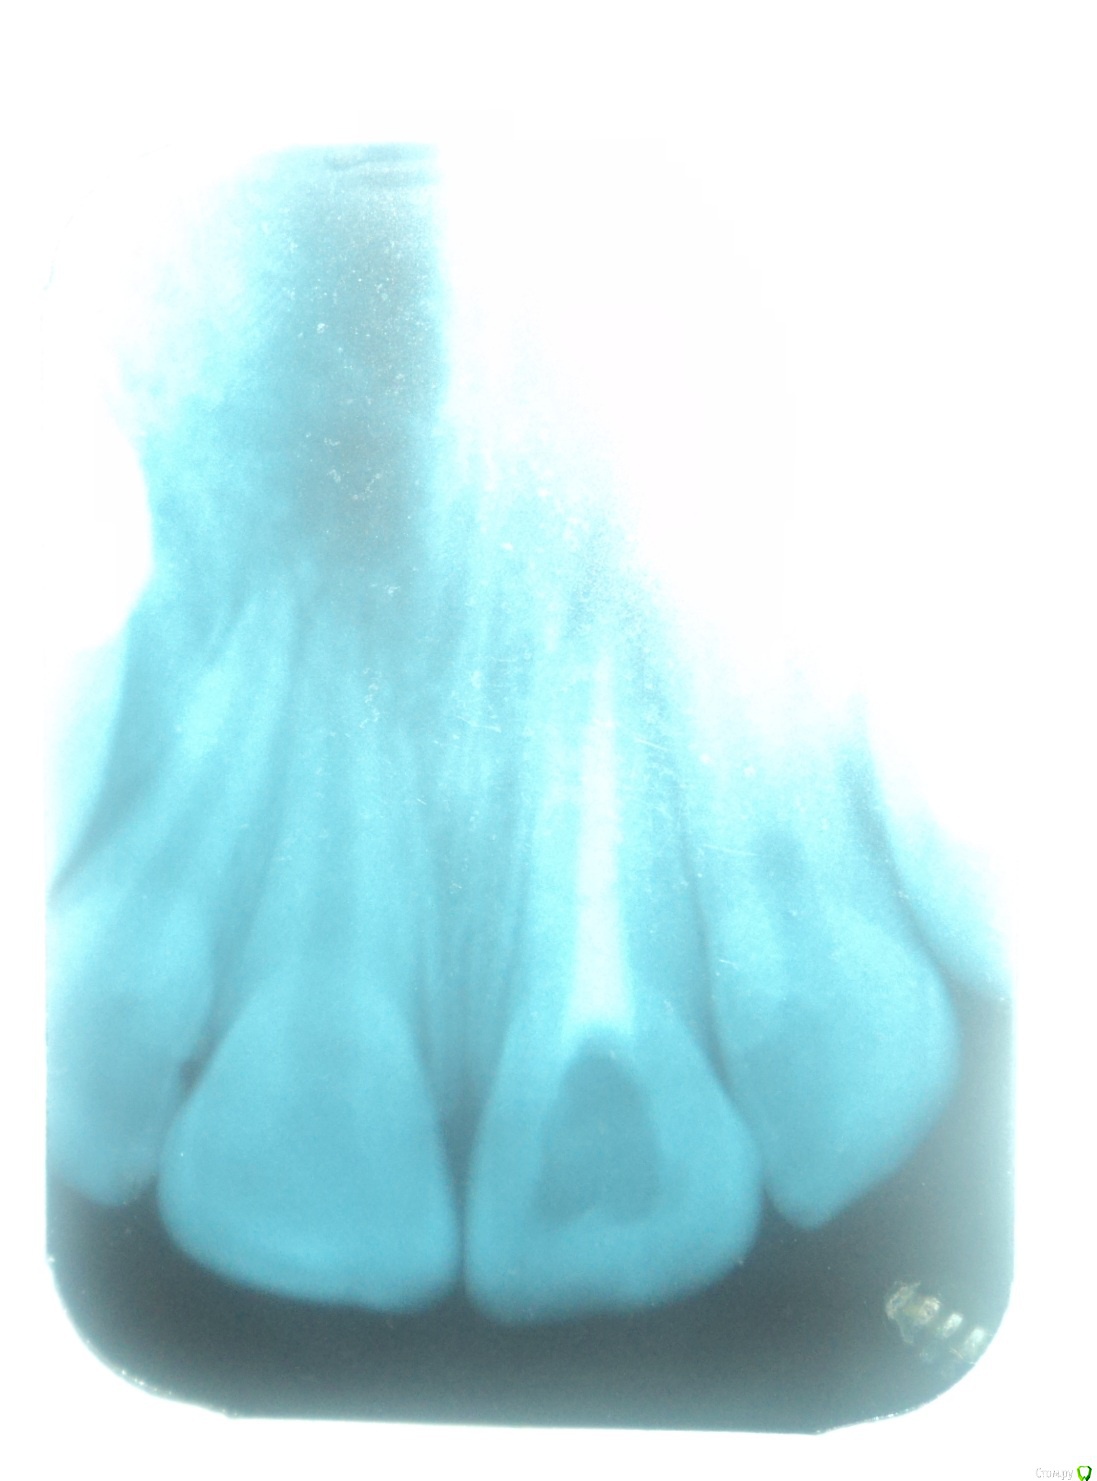

Здравствуйте! Примерно 12 лет назад у меня была травма переднего зуба после чего удалили нерв и  ввели в канал мне сказали метапекс, но по записям вроде не метапекс(фото с записями из карточки и снимки зуба прилагаю)  и запломбировали.  В течении примерно 10 лет (с 22.06.2005) этот зуб меня не беспокоил. Но в следствии ухудшения общего самочувствия я решил сходить к стоматологу. Мне сказали что у меня хронический периодонтит. У этого зуба посинела десна и это меня настораживает. Объясните мне в чем причина посинения десны? И я думаю что, то что происходит в этом зубе негативно сказывается на всем организме во первых как я думаю там может находиться очаг инфекции которая подрывает весь организм во вторых я почитал о действии на организм Метапекса( гидроокись кальция(гашеная известь)) и это действие очень не хорошее. Я не знаю что мне делать с этим зубом удалять или что то там менять чистить? Я не понимаю почему мне после стольких лет когда я пришел на прием мне ничего не сделали с этим зубом ничего не меняли и не чистили сказали все нормально и я ушел .так и должно быть? Жду ответа и совета врачей.

Удалять зуб не нужно. Снимок у Вас размытый получился, поэтому точнее сказать сложно. Посторайтесь либо перефотографировать снимок либо сделать новый.